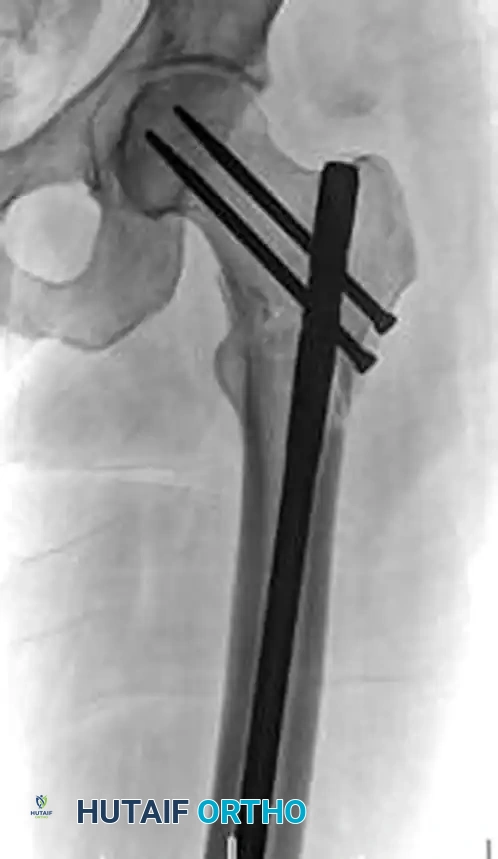

Figure A: Preoperative radiograph demonstrating the classic flexion, abduction, and external rotation deformity of the proximal subtrochanteric fragment.

Figure B: Intraoperative lateral fluoroscopic image without reduction aids, showing persistent malalignment.